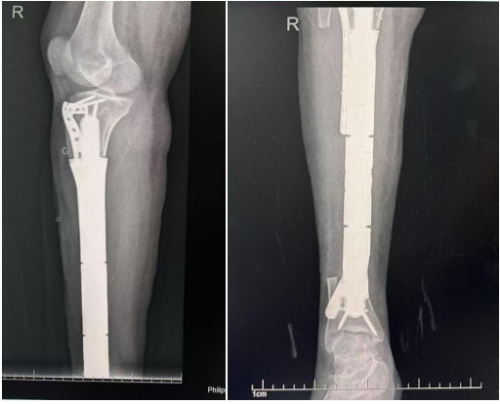

(术前检查显示胫骨肿瘤巨大,累及小腿血管)

手术当天,在手术室、麻醉科团队的配合下,骨肿瘤科主任医师李大森、副主任医师贾俊秀、副主任医师王冀川、主治医师梁海杰、住院医师石惊天等人在术中完整切除患者的胫腓骨肿瘤,保护了临近的血管与神经,并通过导板将假体固定,假体适配度良好。

之后,修复重建外科副主任庹晓晔和主治医师阳跃台上“接力”,利用对侧肢体大隐静脉对患肢的腓动脉—胫前、胫后动脉实施搭桥手术,术中动脉搏动良好。经过专家团队的密切配合,手术宣告成功!当患者从麻醉中苏醒过来,得知手术成功且肢体得到保留时,所有的担心焦虑均化作了幸福的眼泪。

术后,李女士的下肢皮肤温暖、肢体感觉良好、足踝活动自由。术后12天,李女士能够借助拐杖下地站立,在家人和医护人员的帮助下积极开展康复锻炼。李女士也终于卸下了心中的负担,以健全的身体继续着幸福的人生。